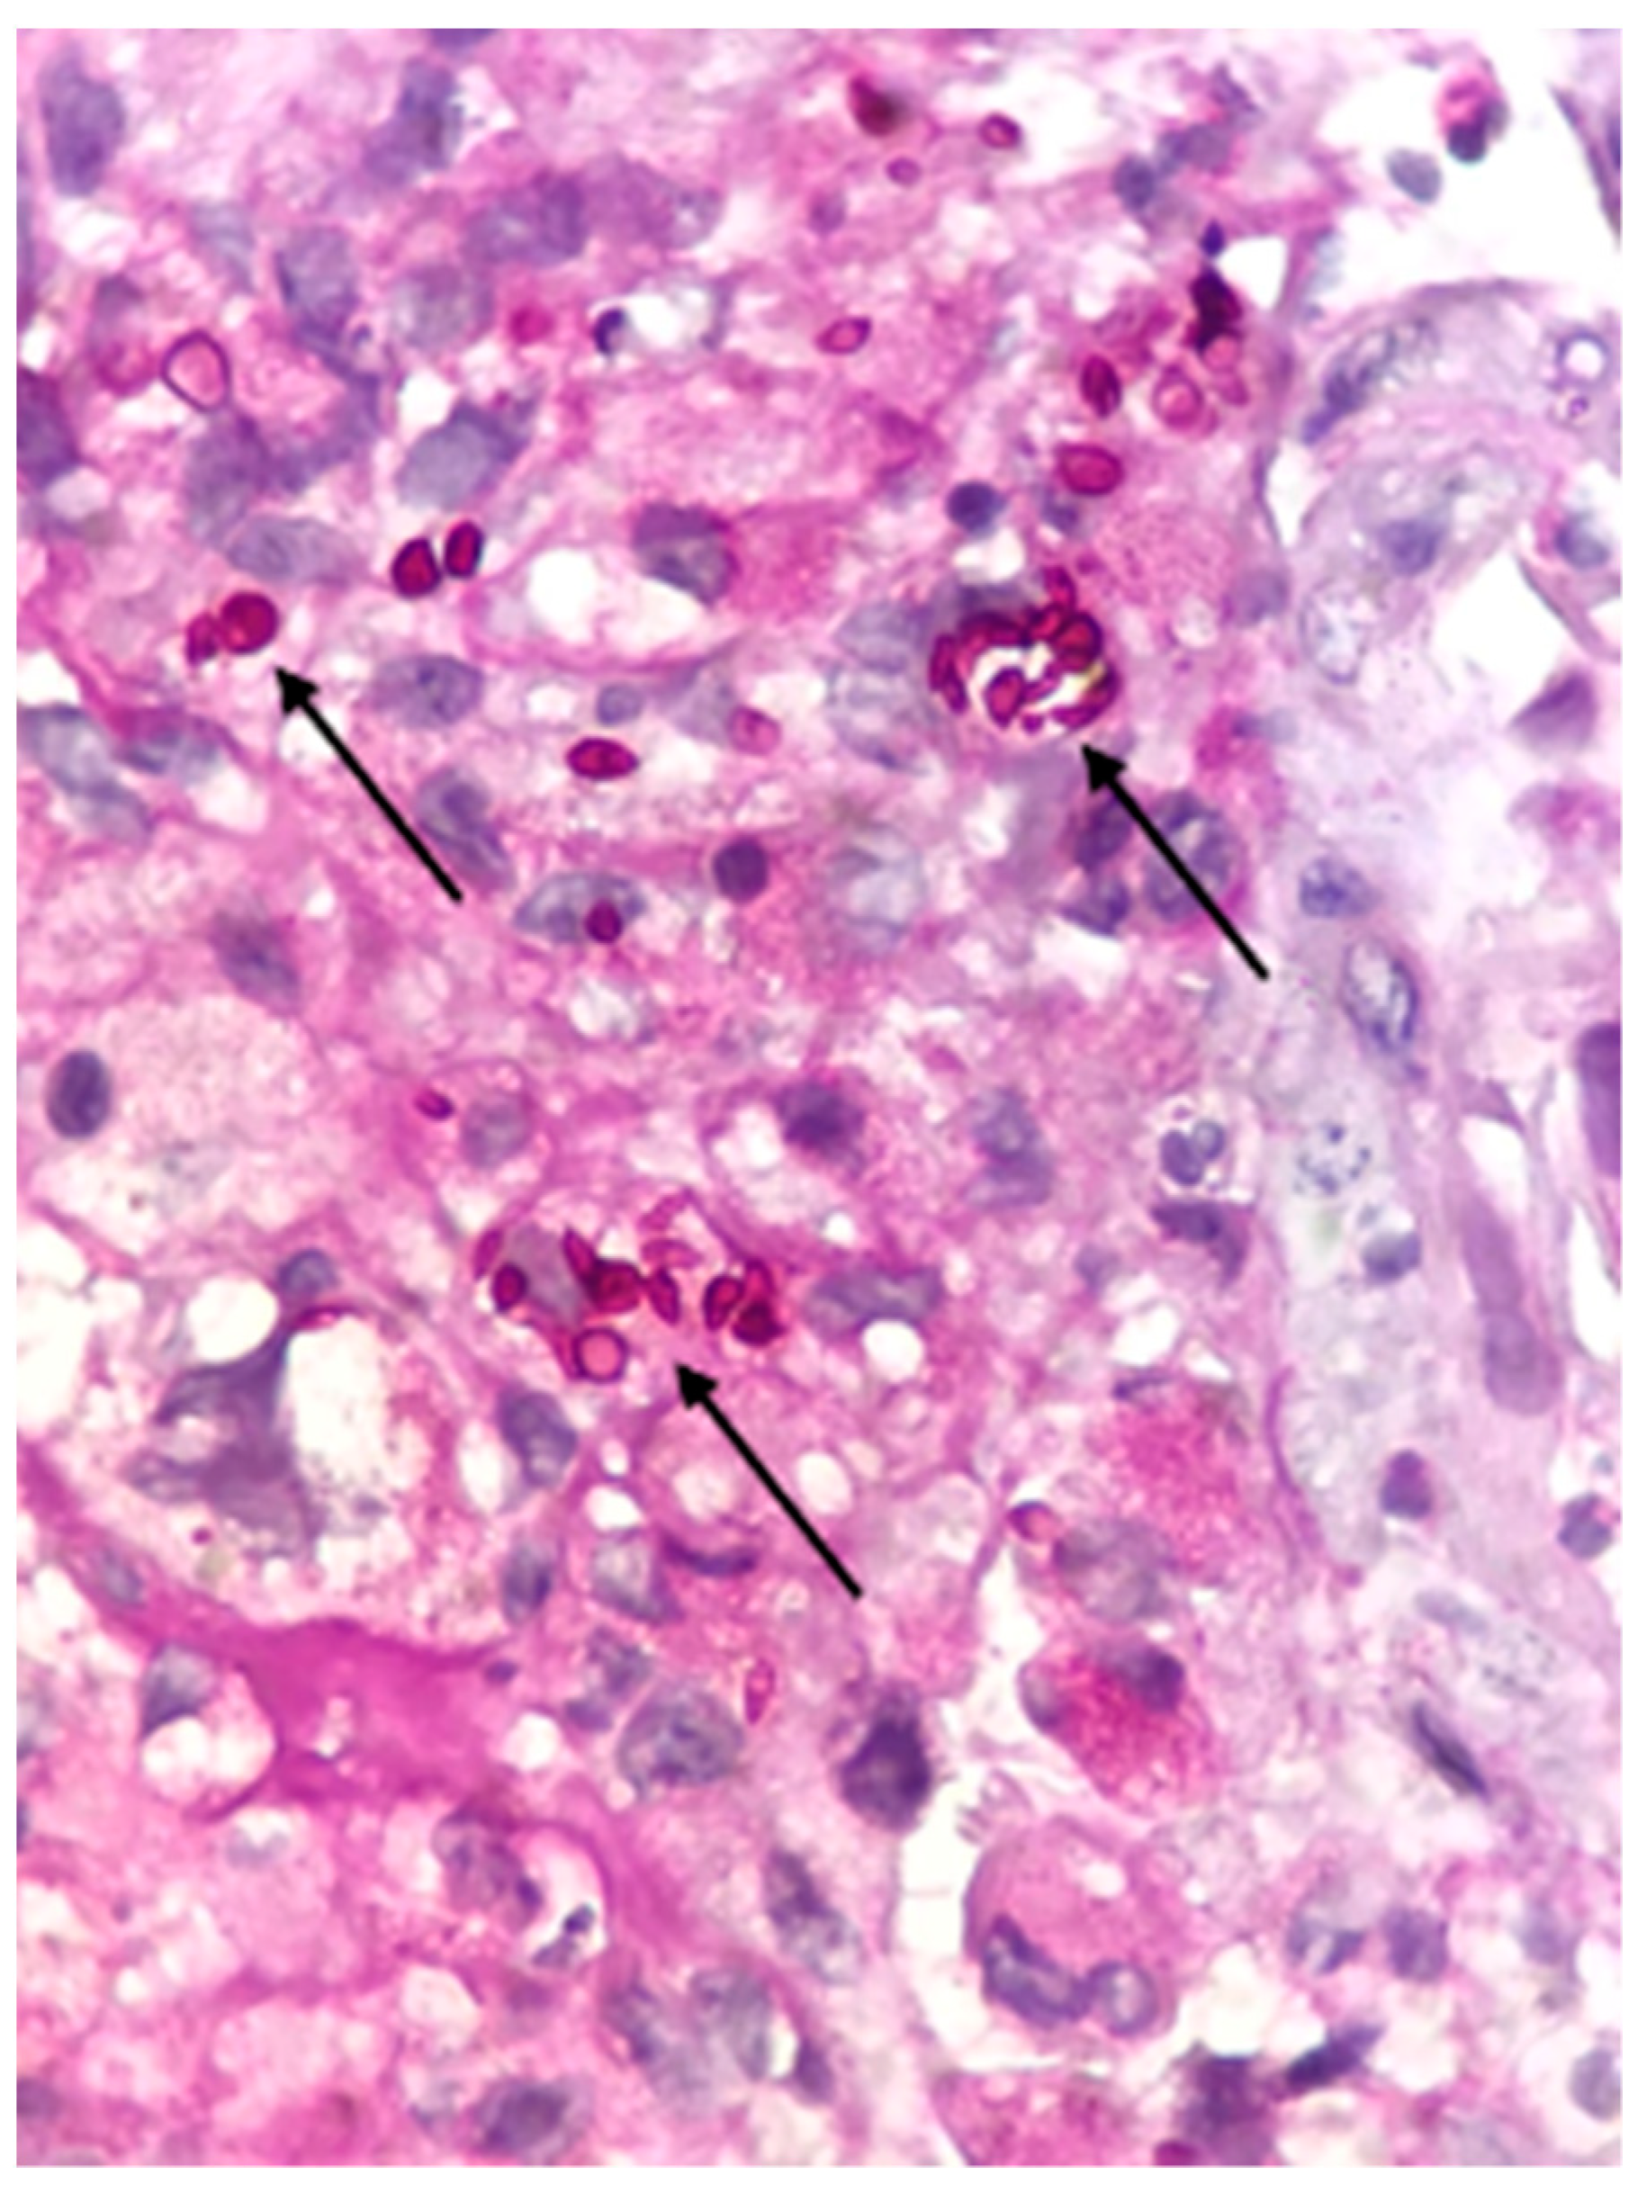

2.1. Case Report